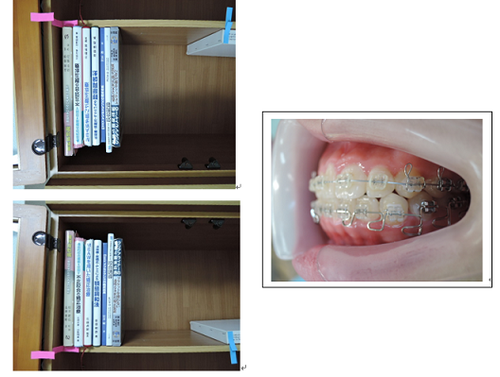

MEAW(マルチループ)

MEAW(マルチループ)はこの〇で囲った部分が一単位で犬歯から奥にある歯をそれぞれ立体的に動かしていく事ができます。

MEAW(マルチループ)を利用して治療中

初診時

治療終了時

初診時から終了時まで咬み合わせに大きな変化が診られますが

歯はどこも抜いていません。